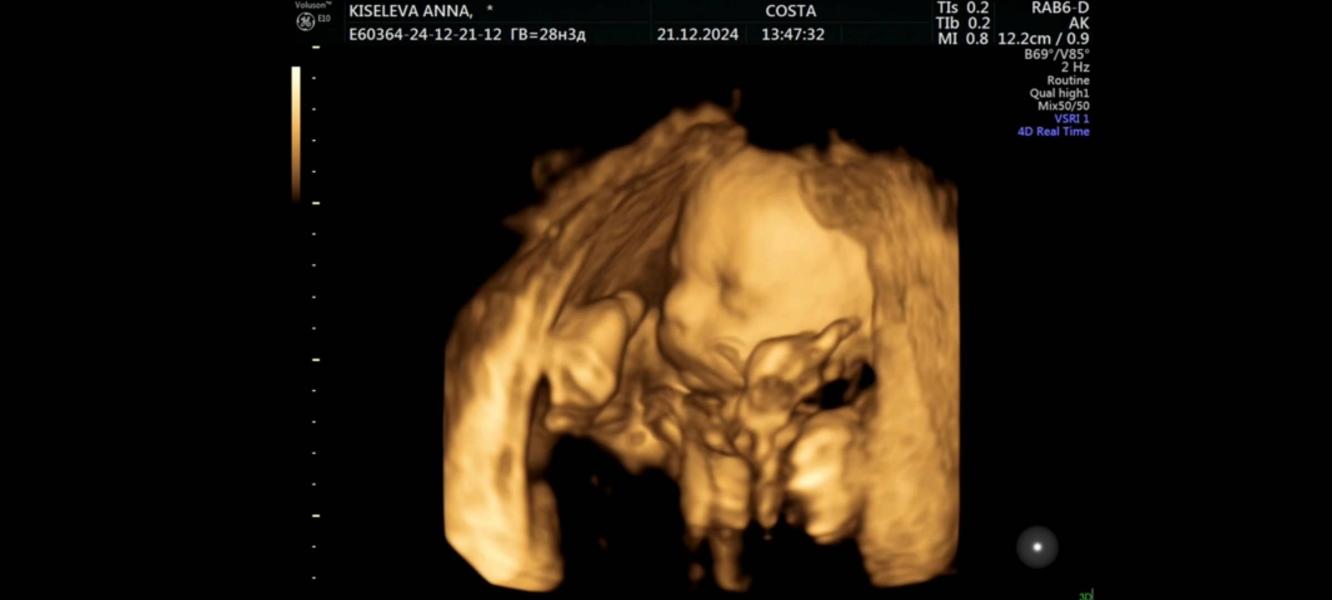

Ах да за пару дней до теста сходила на узи т.к. очень переживала что ковид мог отразится на малыше или кровотоках и тонус стал мучать при хотьбе. Но ттт всё идеально, еле как сфоткали его сладкие щёчки 🥰